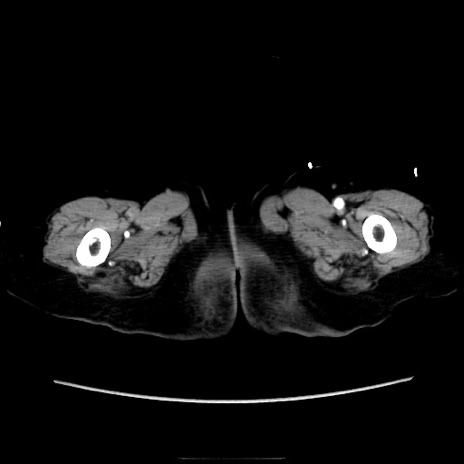

症例40(横断像)

横断像